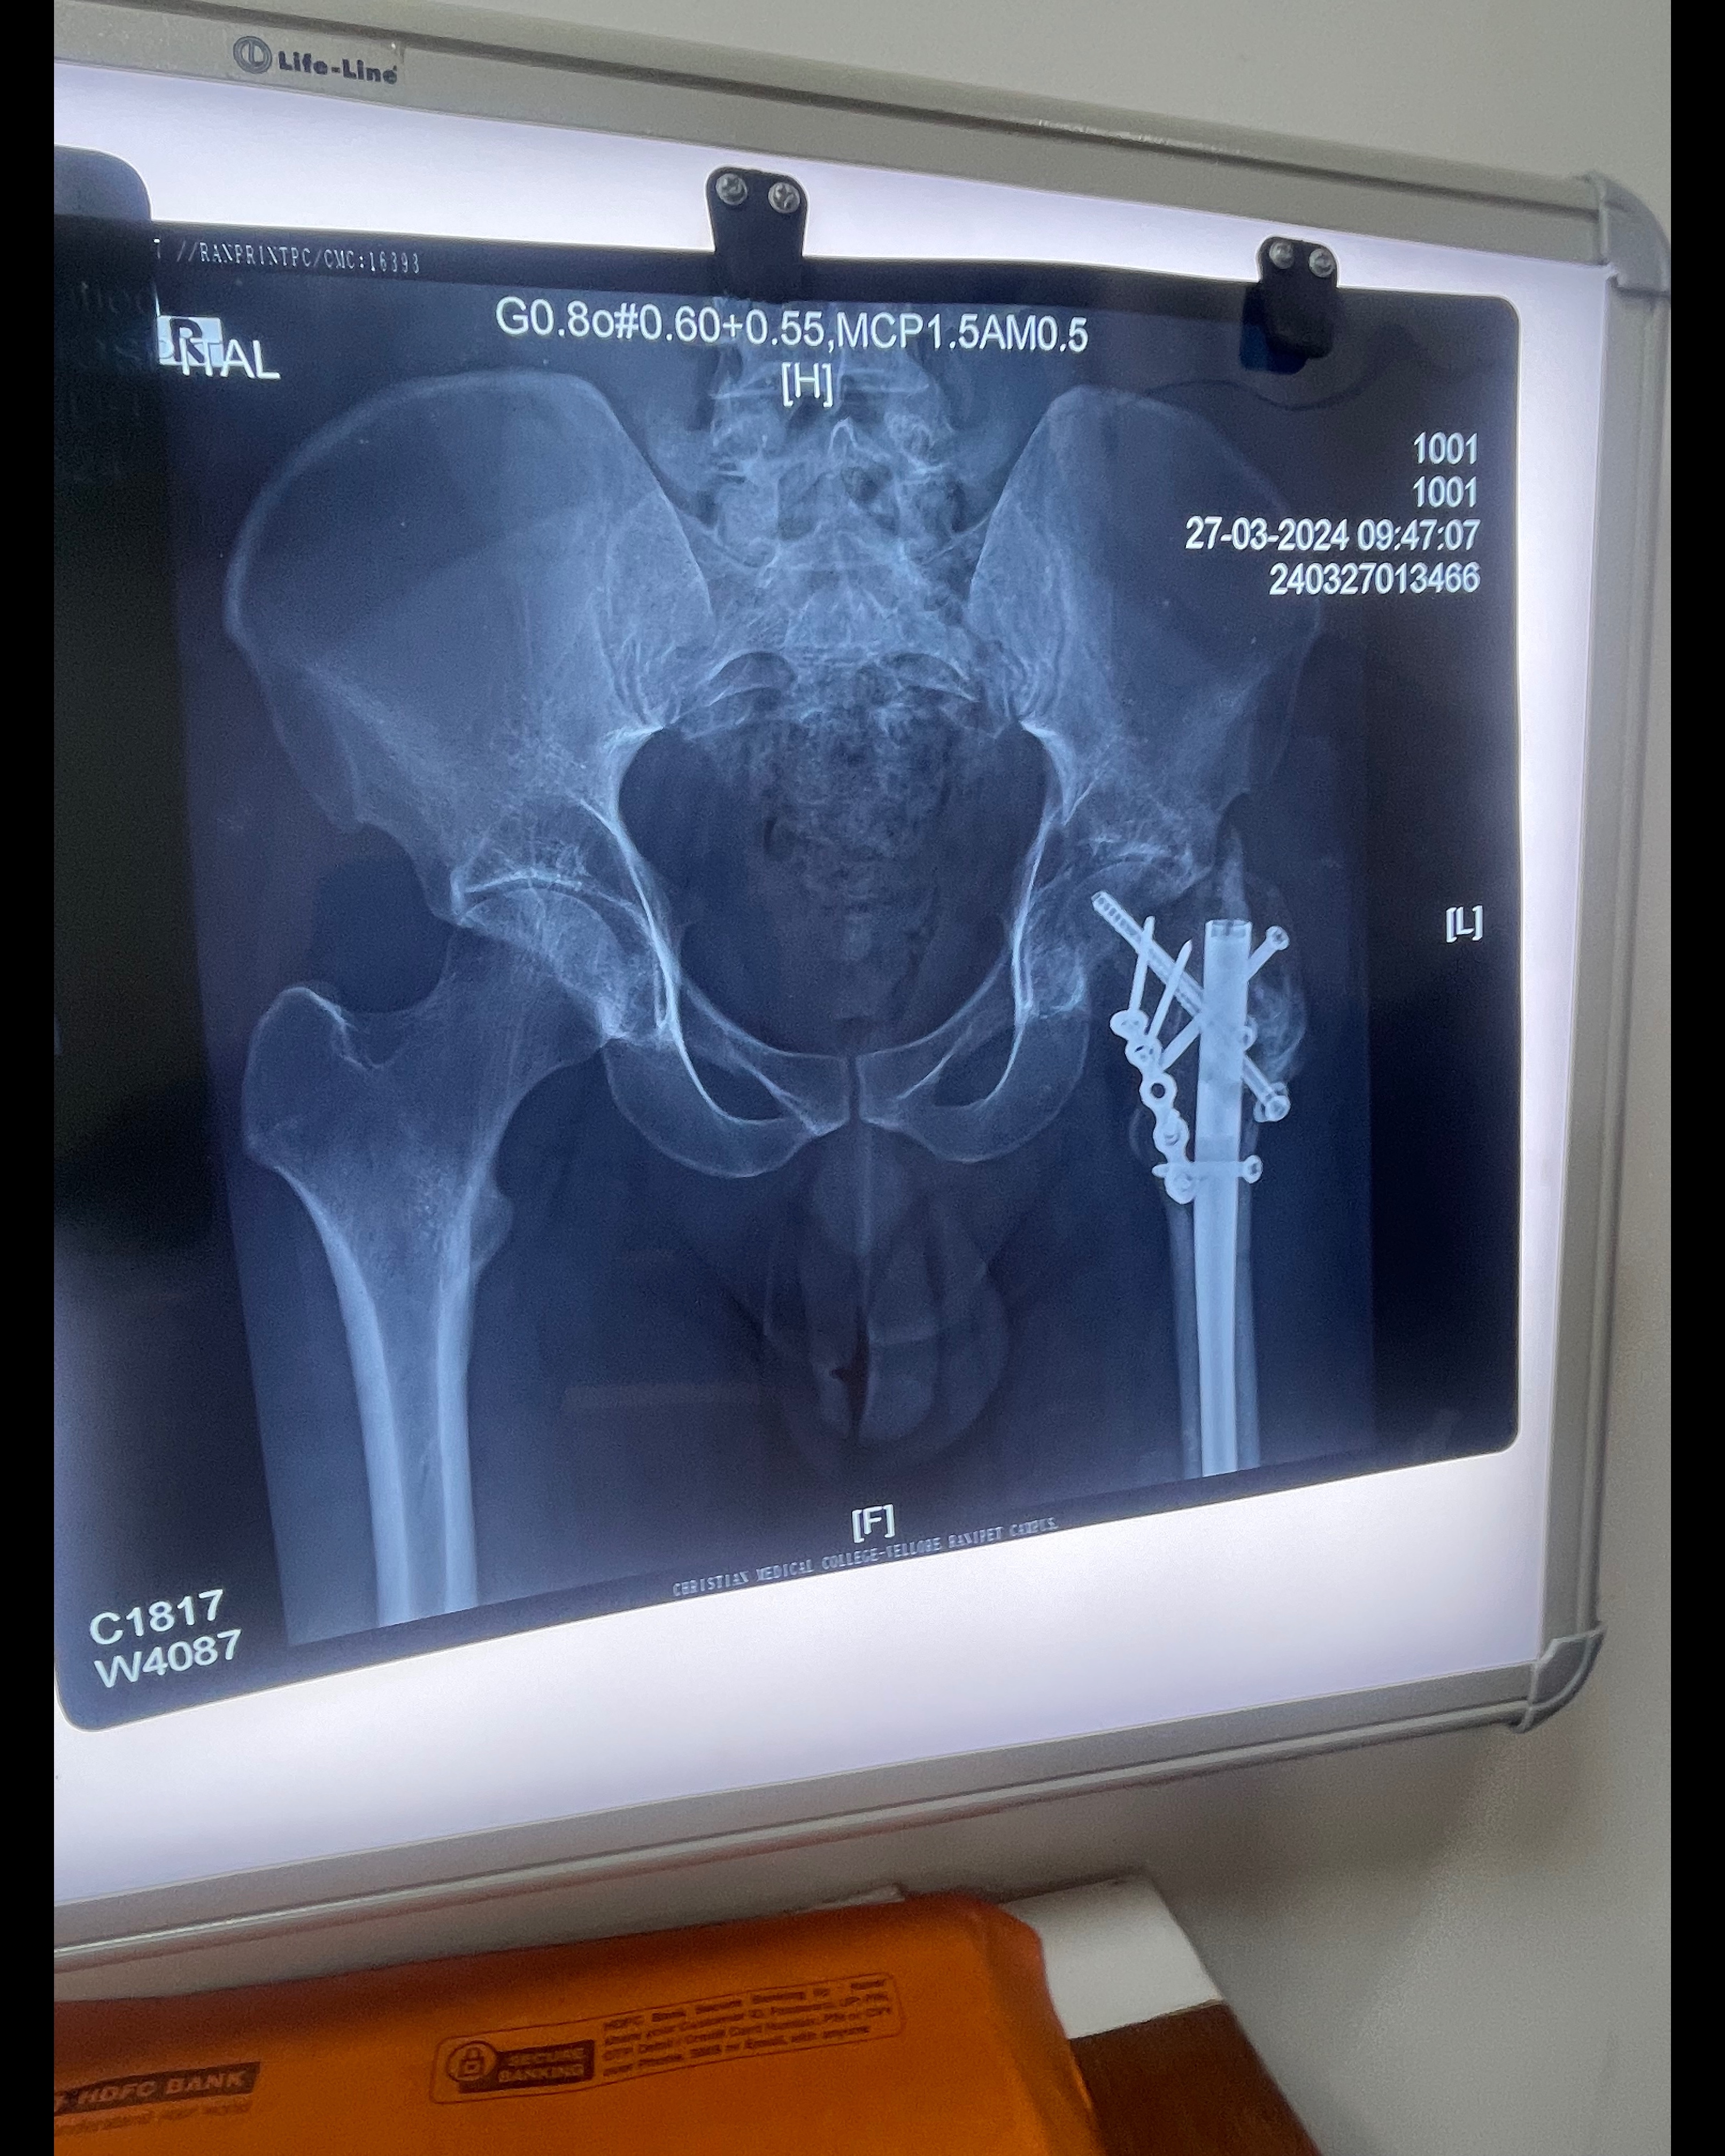

Trauma and post operative physiotherapy and rehabilitation in jk physio and rehab clinics Anna nagar